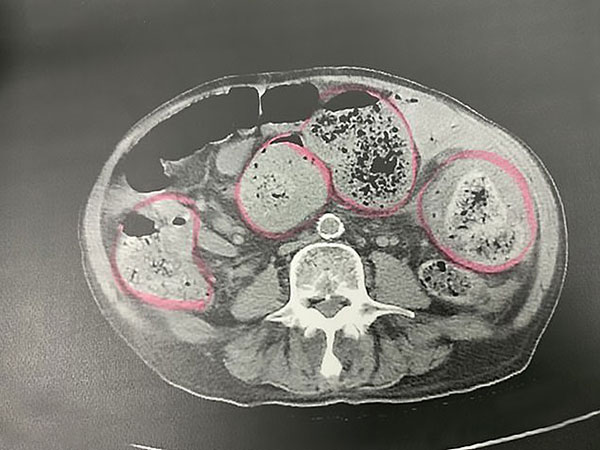

ಆ ವ್ಯಕ್ತಿಯ ಕರುಳಿನಲ್ಲಿ ಮಲವು ತುಂಬಿತ್ತು

ಈ ವ್ಯಕ್ತಿಯು ಅತಿಯಾದ ಮಲಬದ್ಧತೆ ಸಮಸ್ಯೆಯಿಂದ ಬಳಲುತ್ತಿ ದ್ದಾರೆ ಎಂದು ವೈದ್ಯರು ಪತ್ತೆ ಮಾಡಿದರು. ಕರುಳಿನಲ್ಲಿ ಸಂಪೂರ್ಣ ವಾಗಿ ಮಲವು ತುಂಬಿರುವುದು ಪರೀಕ್ಷೆಯಿಂದ ವೈದ್ಯರಿಗೆ ತಿಳಿದು ಬಂತು.

ಶಸ್ತ್ರಚಿಕಿತ್ಸೆ ನಡೆಸಲಾಯಿತು

ಪರೀಕ್ಷೆ ನಡೆಸಿದ ಬಳಿಕ ವ್ಯಕ್ತಿಯನ್ನು ತಕ್ಷಣವೇ ಶಸ್ತ್ರಚಿಕಿತ್ಸೆ ಮಾಡಲು ಕರೆದುಕೊಂಡು ಹೋಗಲಾಯಿತು. ವೈದ್ಯರು ಕಂಡುಕೊಂಡ ವಿಚಾರವೆಂದರೆ ಆ ವ್ಯಕ್ತಿಯ ಕರುಳಿನ ಒಂದು ಭಾಗವು ಅದಾಗಲೇ ಗ್ಯಾಂಗ್ರೀನ್ ಗೆ ಒಳಗಾಗಿತ್ತು ಮತ್ತು ಅದು ಕಪ್ಪಾಗಿತ್ತು. ಇದರಿಂದ ಅಲ್ಲಿನ ಅಂಗಾಂಶಗಳು ಸಂಪೂರ್ಣವಾಗಿ ಸತ್ತು ಹೋಗಿದ್ದವು.

ಕರುಳಿನ 30 ಸೆ.ಮೀ.ನ್ನು ಕತ್ತರಿಸಿ ತೆಗೆಯಬೇಕಾಗಿ ಬಂತು!

ಕರುಳಿನ ಕಪ್ಪಾದ ಭಾಗದಲ್ಲಿ ಅಂಗಾಂಶಗಳು ಅದಾಗಲೇ ಸತ್ತಿರುವ ಕಾರಣದಿಂದಾಗಿ ವೈದ್ಯರು ಶಸ್ತ್ರಚಿಕಿತ್ಸೆ ಮೂಲಕ ಸುಮಾರು 30 ಸೆ.ಮೀ. ಕರುಳಿನ ತುಂಡನ್ನು ತೆಗೆದರು. ಈ ವ್ಯಕ್ತಿಯು ಸಂಪೂರ್ಣ ವಾಗಿ ಚೇತರಿಸಿಕೊಳ್ಳುವ ಮೊದಲು ಅವರನ್ನು 15 ದಿನಗಳ ಕಾಲ ಆಸ್ಪತ್ರೆಯಲ್ಲಿ ಚಿಕಿತ್ಸೆ ಕೊಡಲಾಯಿತು. ಈ ಘಟನೆ ಬಗ್ಗೆ ನಿಮ್ಮ ಅನಿಸಿಕೆ ಏನು? ಕಮೆಂಟ್ ಬಾಕ್ಸ್ ಗೆ ಕ್ಲಿಕ್ ಮಾಡಿ ಬರೆಯಲು ಮರೆಯಬೇಡಿ.